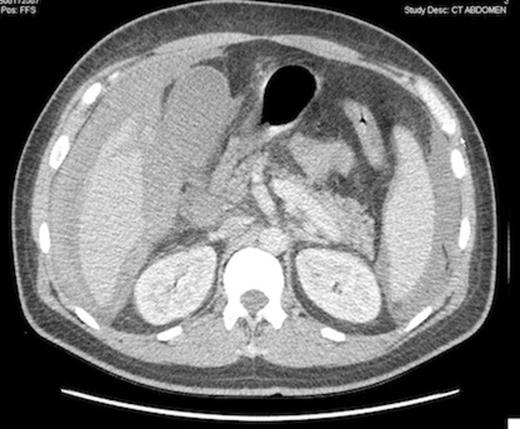

Computed tomography scan showing peritoneal bleeding from hepatic laceration after gallbladder percutaneous transhepatic drainage.

The patient was considered to unstable for a surgical intervention and an emergency percutaneous CT-guided cholecystostomy was done, in spite of a very low platelet count (7 000/mm3). 24 hours later, the septic shock rapidly improved, but hemoglobin level fell down from 83 to 61 g/L. A CT scan showed a bleeding liver laceration with intraperitoneal haemorrhage secondary to the transhepatic percutaneous gallbladder drainage.